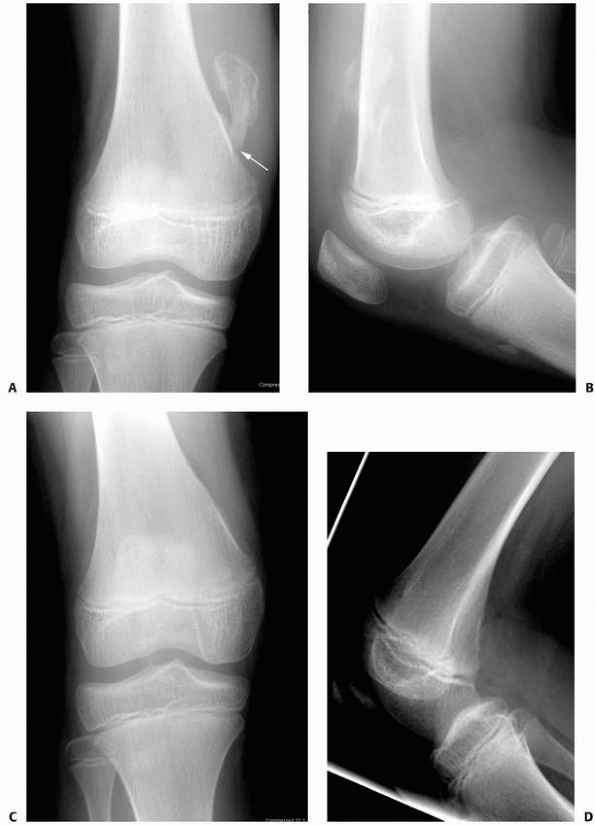

![]() |

FIGURE 6-16 A 13-year-old girl presented with right knee pain following direct trauma to that area 10 days prior. On anteroposterior (A) and lateral (B) radiographs, there was a pathologic fracture through the base of a pedunculated osteochondroma (arrow). The patient was very tender around that area and elected surgical excision. Immediately after excision (C,D),

there was improvement of the symptoms. Four weeks later, she returned to full activities. (Figures reproduced with permission from The Childrens Orthopaedic Center, Los Angeles, CA.) |